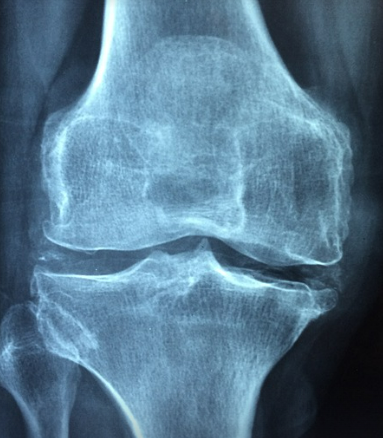

골다공증의 징후와 진단

- 초기 징후: 뼈 통증, 키 감소, 등이 굽는 증상이 나타날 수 있습니다. 이런 증상은 골밀도가 이미 상당히 감소한 상태를 의미할 수 있습니다.

- 진단 방법: 골밀도 검사는 골다공증을 조기에 발견하는 데 필수적입니다. 특히 폐경 이후 여성은 정기적인 검사를 받는 것이 권장됩니다.